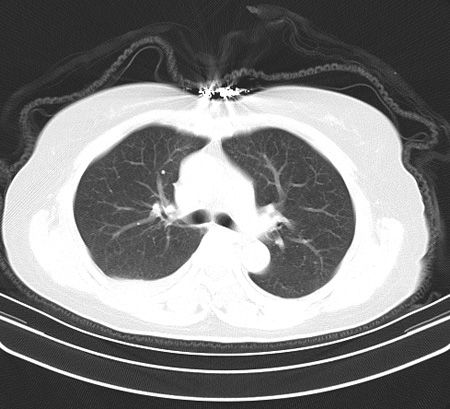

以下是引用余辉在2009-2-19 20:10:00的发言:[br]多考虑急性感染性病变,右中叶尚可见多枚小斑片状影,多为化脓性肺炎,双侧胸腔积液

以下是引用随光逐影在2009-2-19 20:33:00的发言:[br]1)考虑右肺炎症;建议抗炎治疗后复查。2)双侧胸腔积液(以右侧为甚)。

以下是引用花凤凰在2009-2-19 20:46:00的发言:[br]病人有发热,胸痛急性起病,主要病变位于右肺中叶外侧段,呈楔行改变,位于外带胸膜下,考虑为肺梗塞可能!!!!!!!!!!!!!!!!!!!!!!!!!!!!!!!!!!!